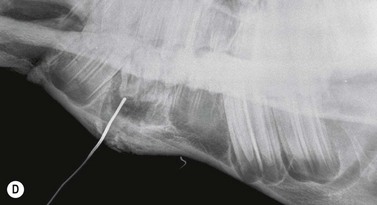

Contrast studies

Placement of a radio-opaque marker over an area of facial swelling and repetition of a radiographic projection (Fig. 13.21) can be an invaluable aid when assessing the clinical significance of radiographic changes. If a cutaneous draining tract is present, as is common in cases of periapical infection of the mandibular cheek teeth or upper 06s and 07s, a blunt metallic probe can be placed into the tract, held in place with tape (Fig. 13.22) and a repeat radiograph taken (Fig. 13.23). This very simple form of contrast study often provides unequivocal evidence that a tooth is infected.

image image

Fig. 13.22 (A & B) A blunt metallic probe placed into a cutaneous discharging tract and secured with radiolucent tape can provide strong evidence as to which tooth is infected in cases of suspected periapical infection.

Fig. 13.23 Lateral oblique radiographs with a blunt metallic probe in place in cases of periapical infection with discharging cutaneous tracts involving the mandibular (A) and rostral maxillary (B) cheek teeth.

Water soluble iodinated contrast media may also be introduced into a tract i.e., fistulography. To avoid leakage, injection should be made through a self-retaining catheter with an inflatable bulb (e.g., Foley) and discontinued immediately resistance is felt.1